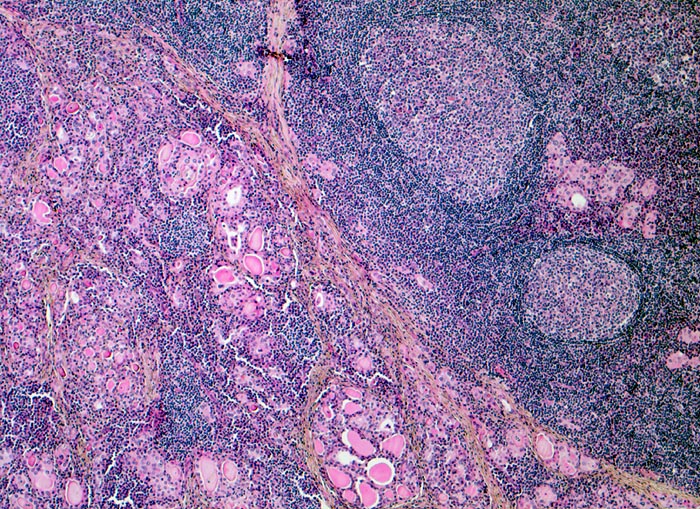

chronische lymphozytäre Thyreoiditis Hashimoto

Mikrofollikuläres Schilddrüsenparenchym mit wenig Kolloid. Das Parenchym wird infiltriert und partiell zerstört durch ein dichtes lymphoides Entzündungsinfiltrat mit sekundären Lymphfollikeln. Stellenweise sind nur kleine Epithelinseln im Entzündungsinfiltrat stehengeblieben.

Die Patientin sucht den Hausarzt auf wegen leichter Schmerzen am Hals rechts. Symptome einer Schilddrüsendysfunktion sind auch auf gezielte Anfrage hin nicht vorhanden. Die Schilddrüse ist deutlich vergrössert. Die laborchemischen Untersuchungen ergeben eine pathologisch erhöhte Konzentration der Peroxidase- und Thyreoglobulin-Antikörper. Die Serumwerte für T4 und T3 sind normal, der Wert für TSH ist erhöht. Die Indikation zur Thyreoidektomie wird wegen der deutlichen Struma gestellt.